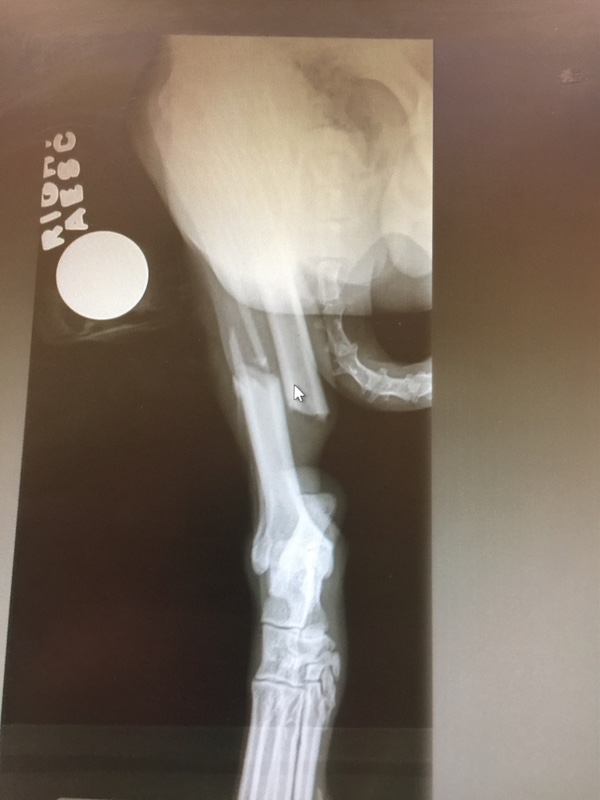

My husband and son quickly got in the car to chase him as he is really fast. Unfortunately, Chase decided to run onto a busy street and ran into the back of a vehicle breaking his leg. He still did not want to be caught and continued running until my son was finally able to catch up to him. They noticed right away that his back right leg was flopping around. They called me as I was away from home and I came home as quick as I could.

Of course this happened on a Saturday afternoon and our normal vet we see is closed. I took him to a local ER veterinarian to X-ray his back leg to see how bad it is. Chase was in shock and they put him on IV fluids and medicine to help calm him down, treat his pain and to finish assessing him.

After taking the X-ray, we discovered he snapped his back right leg in half. The ER vet quoted me $3000 to $4000 to have surgery to fix his break during the week when they had more staff on hand. They would charge around $1500 to $2000 to amputate his back leg if we chose to go that route. She told me low income veterinary offices might charge close to $700 to amputate and I might want to call around on Monday to see what I can find if I chose for them to not operate on Chase.

My veterinarian that I always go has a great board certified orthopedic surgeon that they use. She told me the surgery to save his leg should not go over $2500. I have talked to my vet tech (we have been texting the whole time) and other AKK owners and are encouraging me to try to save his leg if possible!